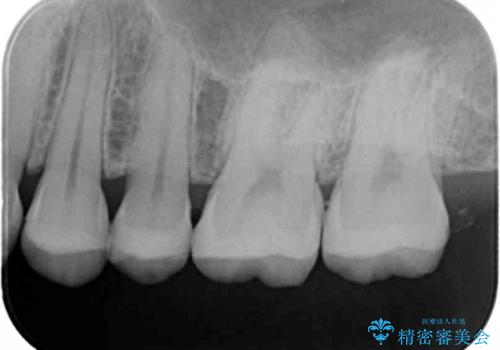

- 銀歯のやり替えをご希望で来院されました。

虫歯を取りつつ銀歯を外し、セラミックインレーでの修復処置を行います。

- 左上567 セラミックインレー:77,000円×3本費用は治療当時の料金となります

処置中に手前の歯の詰め物の不適合が確認されたため、追加で治療していくこととなりました。

銀の詰め物と不適合な詰め物を精度の良いセラミックインレーに変えることができました。